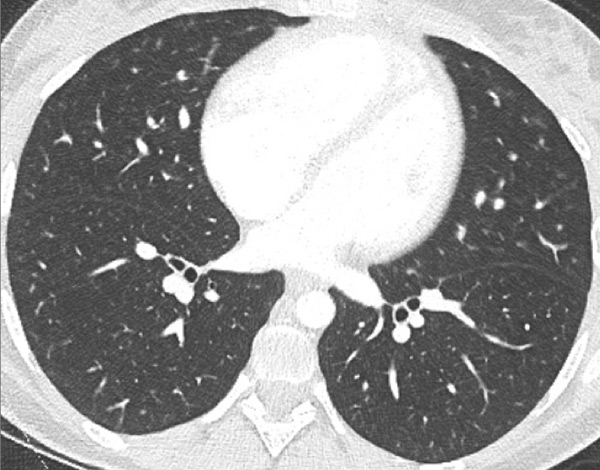

Figure 7

Portopulmonary hypertension in a 16-year-old. No abnormalities were found on morphological computed tomography (A/B), but heterogeneous perfusions were present on the perfusion map (stars, C/D).